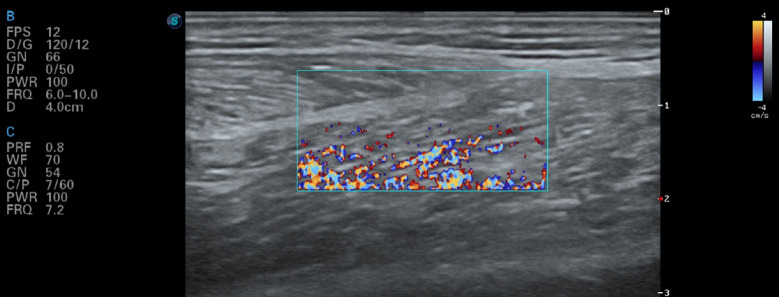

Methods: A randomized controlled trial included 30 participants, assigned to either the GH (n=15) or GS (n=15) group. Each group received treatment on either the right or left side, with one side receiving experimental DN and the other receiving control (sham) DN. The GS method involved a single needle insertion per myofascial trigger point for one minute, while the GH method used multiple rapid needle insertions over two minutes without needle retention. Measurements were taken before therapy, 5 minutes post-DN session (post-5min), 24 hours post-session (post-24h), and 7 days post-session (post-7d). Muscle tension (MT) and muscle stiffness (MS) were measured with a myotonometer, pressure pain threshold (PPT) with an algometer, maximum isometric strength (Fmax) with a handheld dynamometer, and transcutaneous perfusion (PU) with laser Doppler flowmetry. Power Doppler Score (PDS) and minor adverse events were also recorded.

Results: Results showed that GH led to significantly higher MT and MS values at post-24h and post-7d (p<0.001). In contrast, GS showed greater PPT and Fmax at post-5min, post-24h, and post-7d (p<0.001). Additionally, GH exhibited higher PU values at post-5min and post-7d (p<0.001), while GS showed higher PDS values at post-5min and post-24h (p<0.001).

Abstract Image